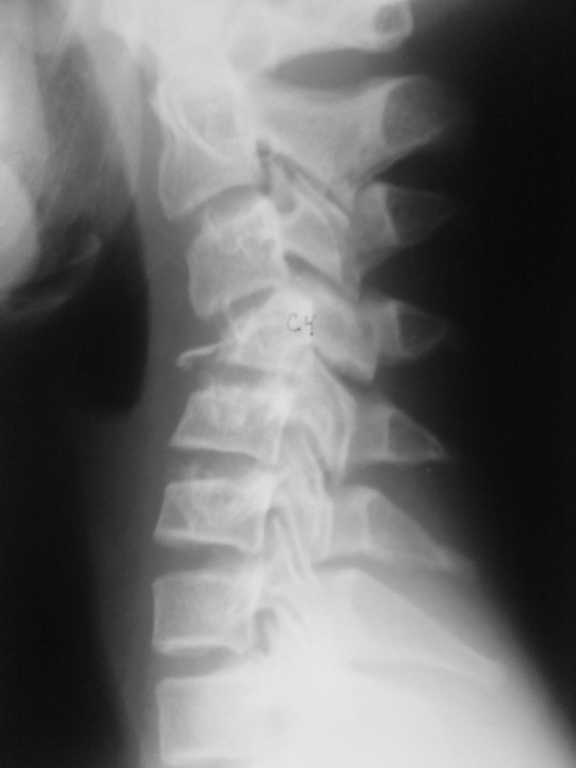

Уважаемые коллеги! Помогите определиться с тактикой лечения. Подросток 14 лет получил травму 2 недели назад , нырнул в реку , вынырнул и на голову прыгнул другой подросток.

Последний госпитализирован в краевую детскую больницу в травматолого-ортопедическое отделение. DS Закрытый нестабильный неосложнённый тип В3 компрессионно- оскольчатый переломо-вывих С4, перелом обеих дужек, перелом сутавного отростка, двухсторонний сцепившийся вывих С4. При поступлении наложен галоапппарат, проводилась галотракция. Представлены Rg-снимки до и после галотракции. Необходимо решить вопрос : необходим ли передний корпородез если да , то когда?

Больному выполнена Rg- ШОП, КТ_ до галотракции, после галотракции.

Уважаемый Вячеслав! Для определения тактики лечения необходимо: Спондилограммы в двух проекциях, до и после Ваших манипуляций, КТ, по возможности и МРТ. В каком состоянии CV и CVI? Вероятно, имеется стеноз позвоночного канала на уровне CIV, который придется устранять.

Мы бы выполнили переднюю декомпрессию, открытое вправление вывиха и передний расклинивающий спондилодез (кифоз после полноценной резекции тела удастся устранить) CIII-V + пластинка.

Передний корпородез необходим (оптимально с использованием шейной пластины). Галотракция на мой взгляд эффективна и можна будет обойтись одним передним доступом. Прогрессирование кифотической деформации на мой взгляд не так связано с доступом (задний доступ был бы необходим для вправления вывиха, который по представленным снимка вроде как вправлен. Оптимально было бы посмотреть все сканы, а не 3Д реконструкцию), как с использованием пластины, которая и должна обеспечить фиксацию до образования костного блока.

Victor 06 Сентябрь 2010, 02:51

Как минимум частичная корпэктомия с4, трансплант и пластина. В идеале если есть возможность + задний доступ и стабилизация.